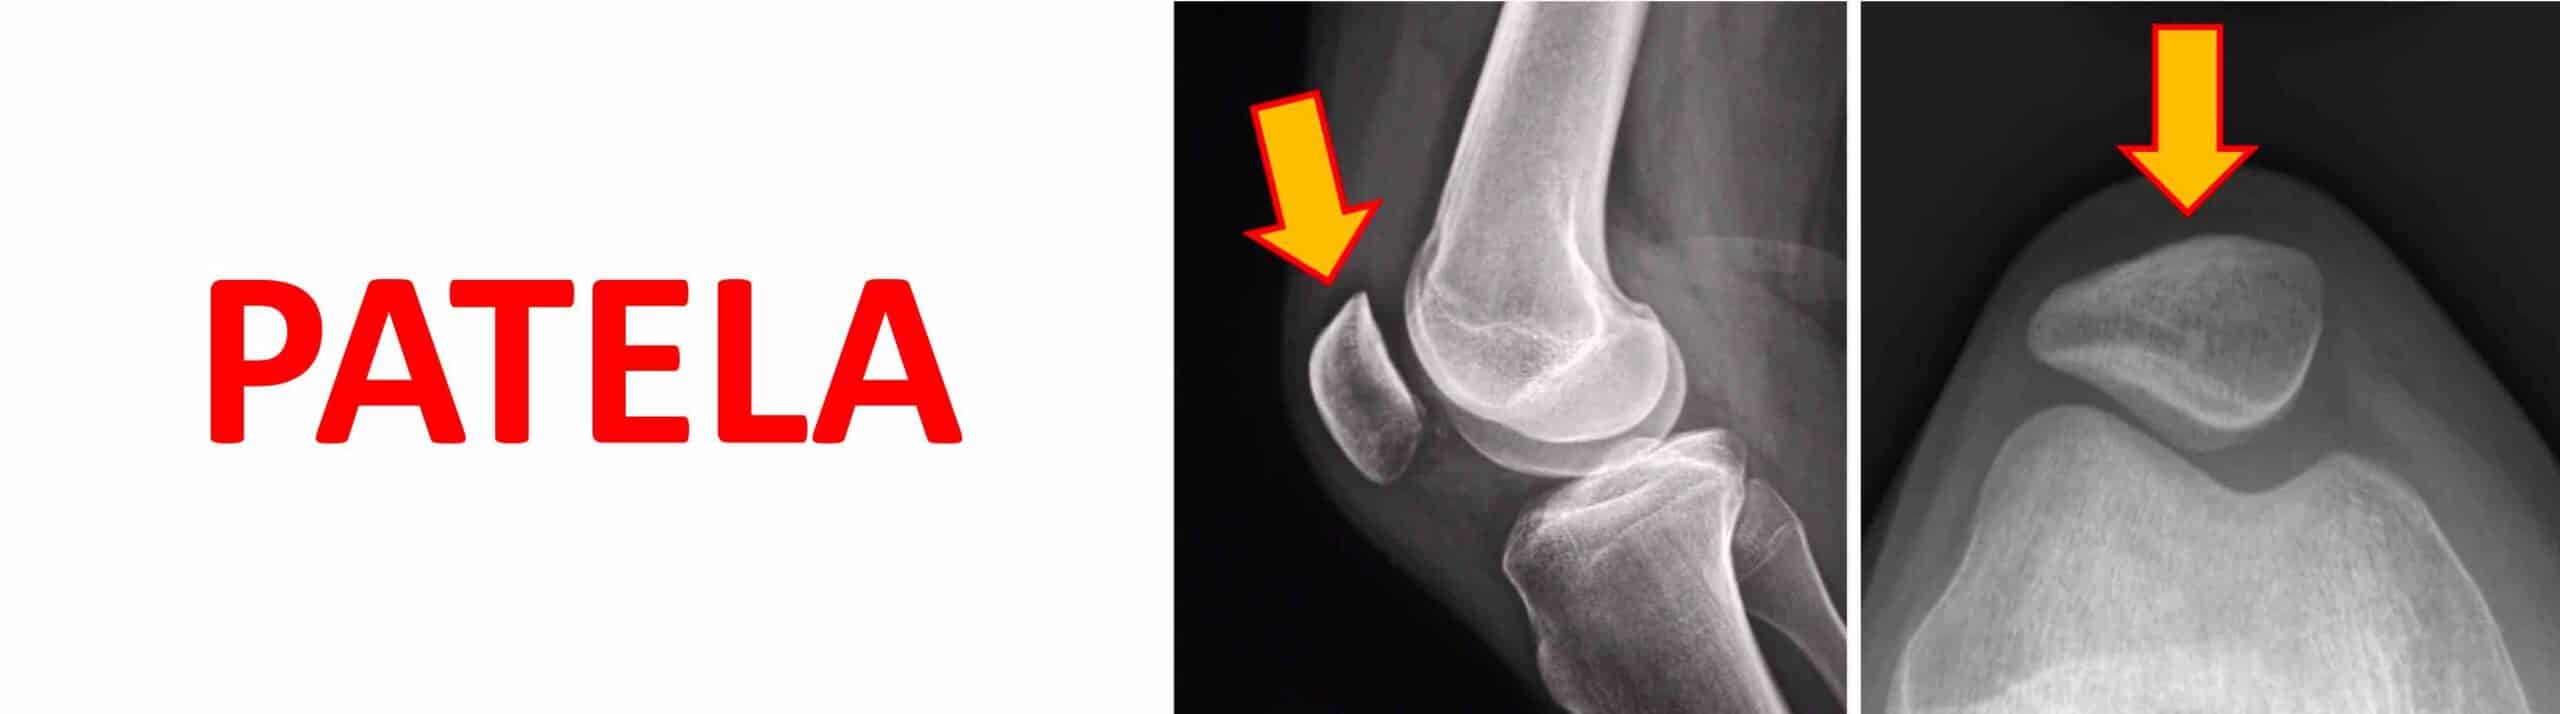

PATELA

A patela, chamada antigamente de rótula, é o maior osso sesamóide do nosso corpo. A patela está localizada na frente do joelho, inserida dentro do tendão do músculo quadríceps femoral. As principais funções da patela no joelho são: proteger a região anterior da articulação, melhorar a eficiência biomecânica do músculo quadríceps femoral para a extensão da perna sobre a coxa e reduzir o atrito entre o tendão quadricipital e a tróclea femoral. A ausência da patela ou sua malformação pode causar instabilidade, dor, luxações e limitação funcional do joelho.